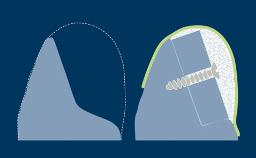

Sinus floor elevation can be performed by lateral window or transcrestal approaches.

This module will focus on the surgical treatment concept and steps for the transcrestal sinus floor elevation technique.